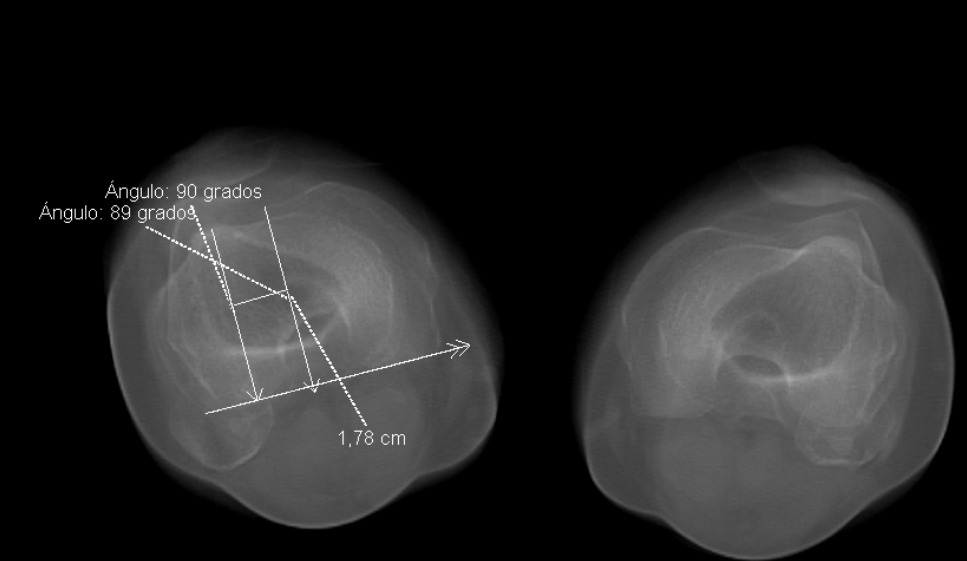

Screenshots

Before before After after